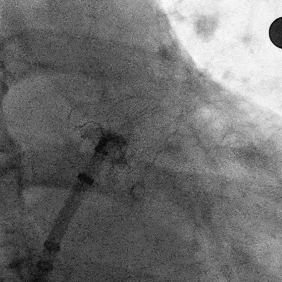

Lefort封堵器展开后DSA评估和调整

肝位即刻造影,位置合适,上下缘无造影剂漏

牵拉时造影,有明显回弹,牵拉后位置无移动

封堵器未肩部

锚定区压缩比10%